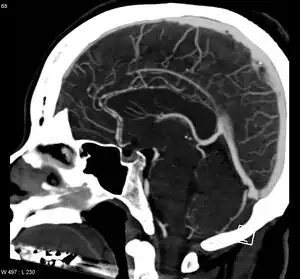

| Significant beading of all intracranial arteries, best demonstrated in the anterior cerebral arties due to RCVS. | |